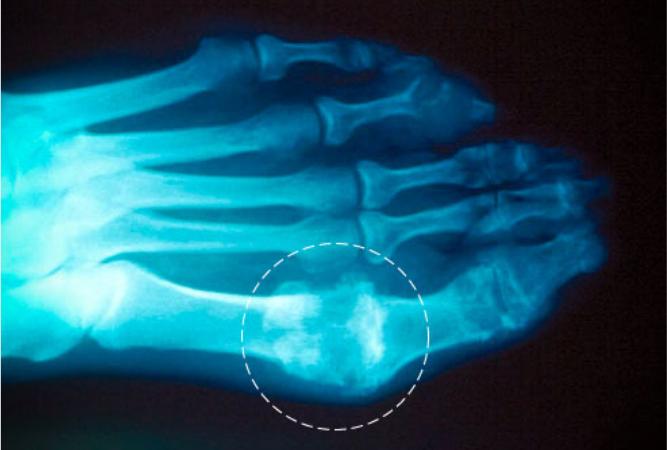

痛风性关节炎的诊断

当病人表示自己有过关节炎痛苦反复发作的经历,尤其是病发部位在脚趾根部或脚踝和膝盖时,大多数是痛风。确认痛风最可靠的方法就是检测关节液中的尿酸盐结晶(通过关节吸引术获取)。检测主要流程如下:先进行局部麻醉;然后利用无菌技术,用注射器或针管将关节液从发炎关节处抽出(吸出)。